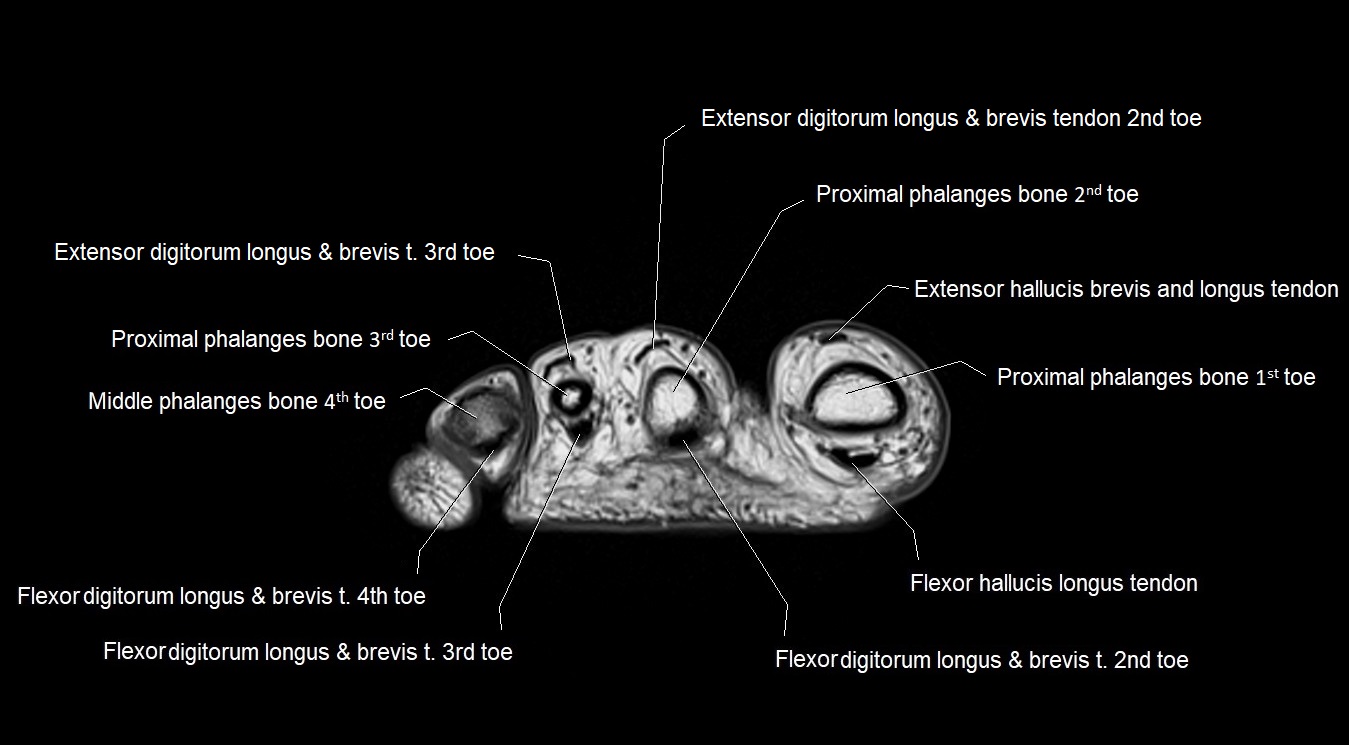

MRI image